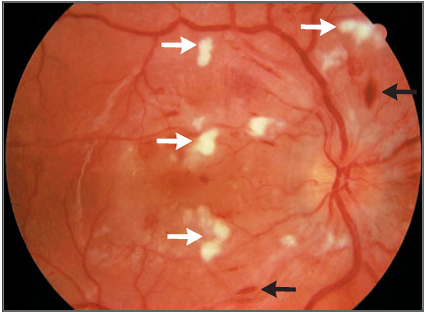

Hình 4. Bệnh võng mạc tăng huyết áp mức độ trung bình (Nguồn: New England Journal of Medicine). A: xuất huyết võng mạc (mũi tên đen) và xuất tiết bông (mũi tên trắng). B: xuất tiết bông (mũi tên trắng) và bắt chéo động tĩnh mạch (mũi tên đen)

- Xuất tiết bông: hay gọi là xuất tiết mềm là những đám trắng bờ không rõ nằm nông che lấp các mạch máu hay nằm gần những mạch máu lớn

- Xuất tiết cứng: là những đám màu vàng nằm sâu, ranh giới rõ thường ở cực sau. Chúng có thể sắp xếp theo hình nan hoa lan tỏa ra quanh hoàng điểm tao thành sao hoàng điểm. Đôi khi chúng tập trung lại tạo nên một đám thâm nhiễm lớn.